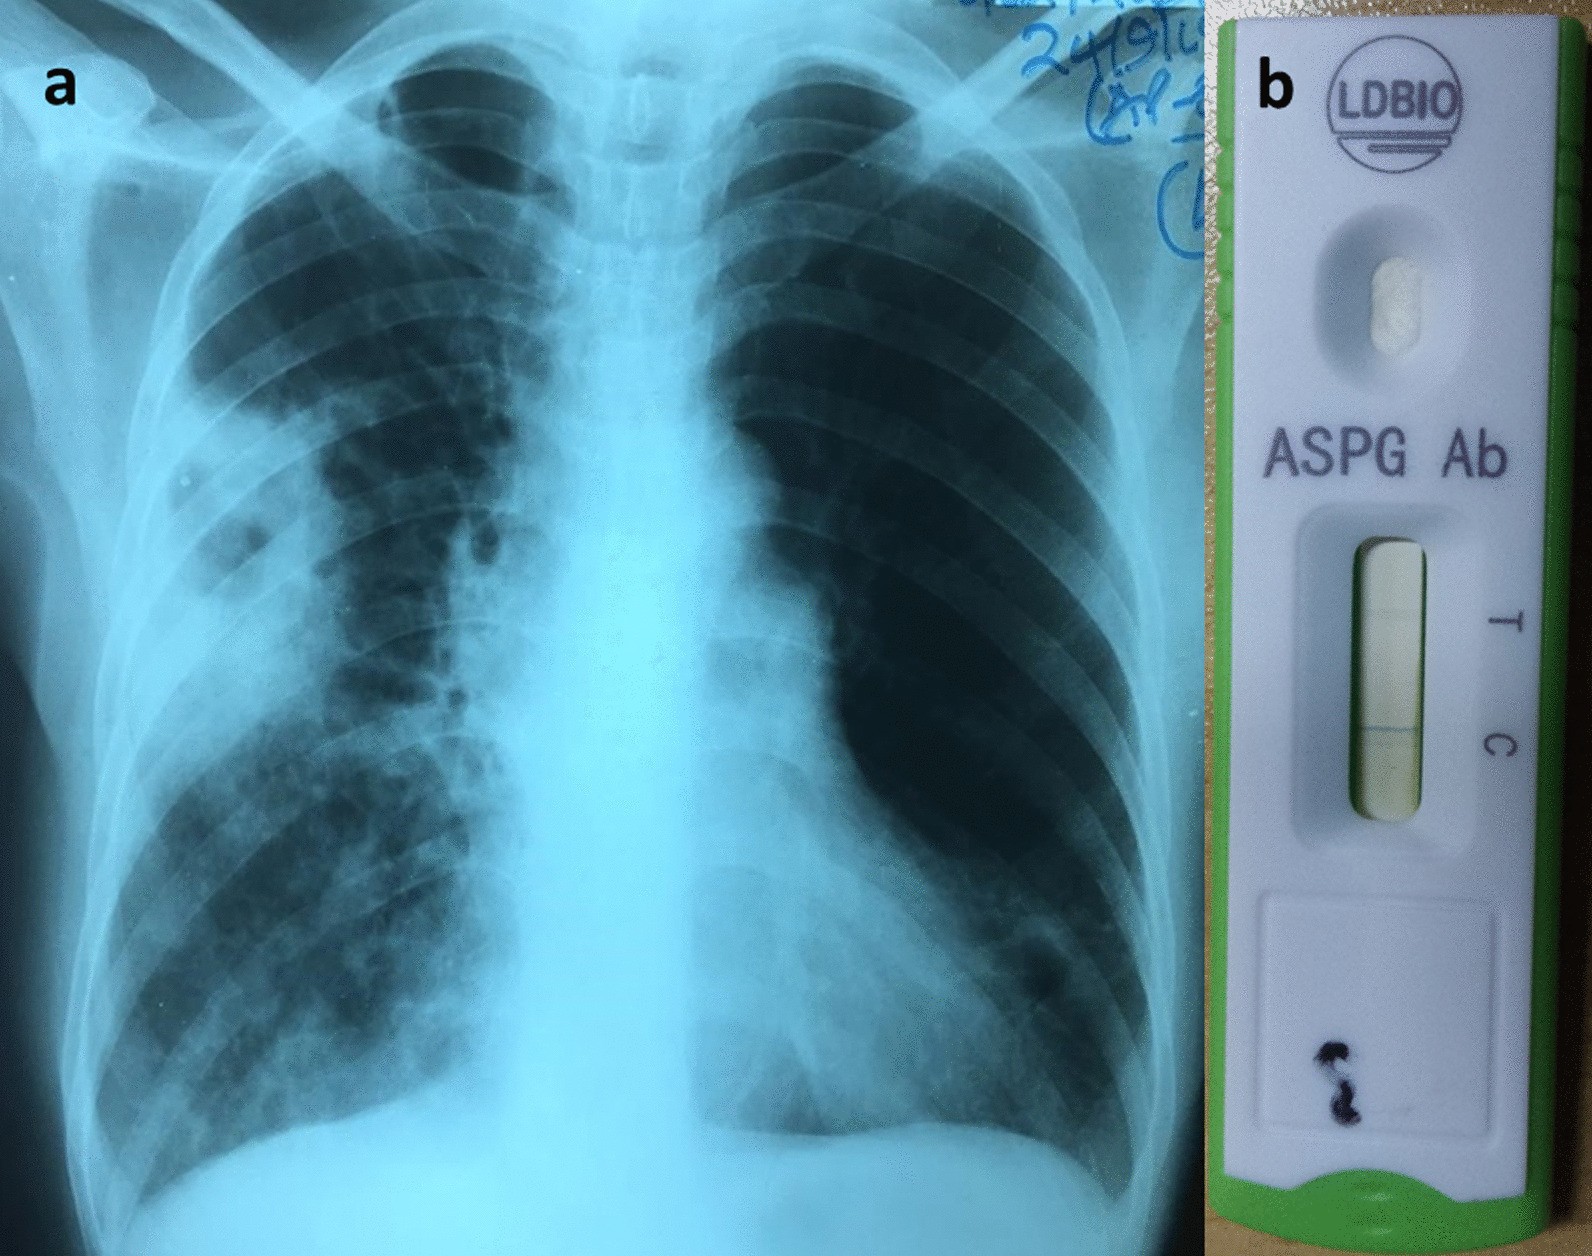

Fig. 2From: Misdiagnosis of chronic pulmonary aspergillosis as pulmonary tuberculosis at a tertiary care center in Uganda: a case seriesCase 2. a Chest x-ray showing a thick-walled cavity with an intrinsic mass in the right middle zone surrounded with patchy opacities medially and inferiorly. b Positive Aspergillus IgM-IgG LFDBack to article page